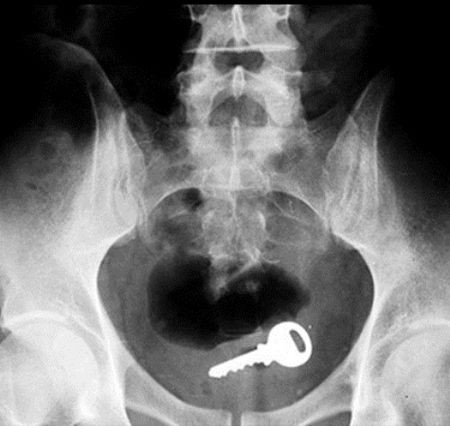

3. Een sleutel

Een nieuwe plek om te zoeken als je de huissleutel kwijt bent. Niet vergeten om ook even in de kont te zoeken want je weet het maar nooit.